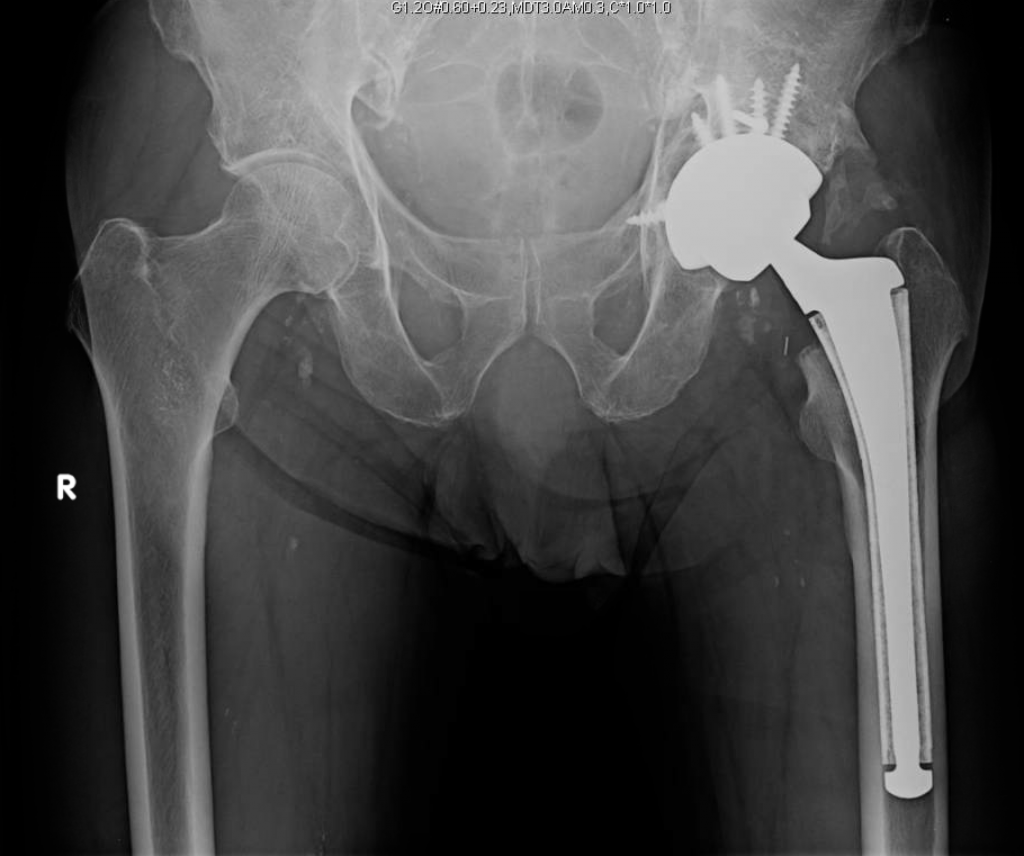

This is a 78 year old male who fell and sustained an anterior column acetabular fracture. The patient had a history of peripheral vascular disease and previously underwent femoral-femoral artery bypass. This precluded him from having a traditional open reduction internal fixation (ORIF) of the acetabulum through an ilioinguinal approach.

The patient underwent simultaneous acetabular ORIF and complex THA reconstruction by Dr. Darwin Chen and Dr. David Forsh (Chief of Orthopaedic Trauma). A Kocher-Langenbeck approach was used for exposure. The anterior and posterior columns were secured together using a single posterior-to-anterior screw just superior to the acetabulum. An acetabular shell was implanted with excellent inherent stability, followed by screw fixation into the superior dome as well as inferiorly into the ischium.

After a period of limited weight bearing, the patient was able to return to full function without deficits.